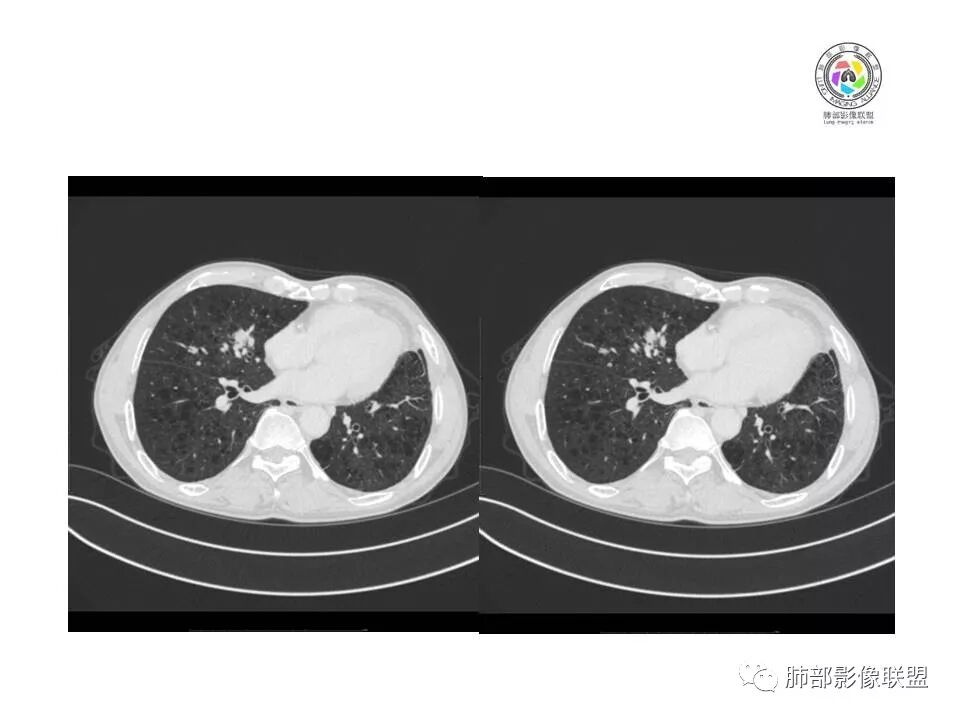

患者老年男性,间断咳嗽、咳痰伴痰中带血2个半月就诊,胸CT:右肺中叶内侧段占位性病变,病变可见分叶,周围可见结节影。病灶内可见厚壁空洞,洞壁光滑,未见洞壁结节,右肺中叶内侧段近肺门处支气管壁增厚。诊断:考虑结核,鉴别:肺癌,建议痰找抗酸杆菌、支气管镜检查

老年人,右肺中叶內侧段结节病灶,内见不规则空洞,近端可见引流支气管,其支气管壁增厚。结节病灶周围可见卫星灶,考虑肉芽肿病变,结核可能。

肺气肿明显

中叶内侧段结节

少许细小结节

LCNEC最常见的影像特征包括:(1)肿块发生部位:周围型肺癌为主,少数发生于肺中央。(2)肿块大小及形态。因肿瘤细胞生长迅速常形成较大肿块,因此其体积一般较大,直径常在3~10cm范围内,病灶常为不规则形软组织肿块。(3)肿块边界。多数学者报道大多数肿块边界清晰,边缘呈分叶状,毛刺征及“胸膜凹陷征”少见,认为与该病对周围组织浸润较轻及较少产生纤维瘢痕组织牵拉有关联。(4)肿块密度、强化特点及代谢情况。据文献报道,该类肿瘤因体积较大CT上常见软组织肿块,且多数密度不均匀,内见囊变坏死区,增强后呈轻或中度不均匀强化(可见强化者占75.7%),认为其强化特点与其内部肉眼可见坏死灶和肿瘤较大直径有关。(5)伴随症状及远处转移。该病恶性程度高,侵袭性强,常侵犯邻近结构,如胸膜、心包、邻近骨质或纵隔内组织等,易出现纵隔淋巴结转移,部分发生肺内及远处转移,少数早期可出现广泛远处转移。